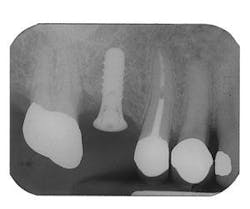

Figure 5 - Placement of three ITI implants

Figure 9 - ITI implant placement Tooth No. 3

Figure 10 - Restored implants